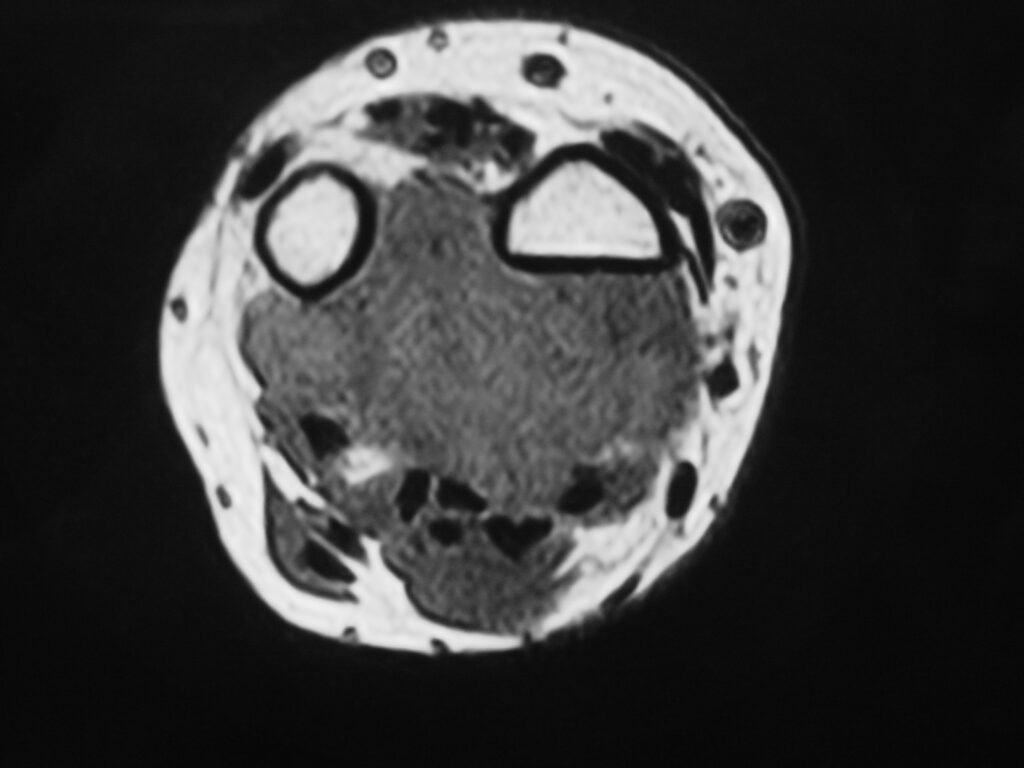

MRI

Shows multiloculated, heterogeneous mass.

“Triple Signal Intensity sign”; hypointense, isointense and hyperintense with fat on T2 – weighted MRI imaging. This sign is present in 30 to 50% of the cases. (Fig.3)

Under contrast enhancement Synovial Sarcoma appears heterogeneous and demonstrate areas of nodular enhancement.

In approximately 30% of cases a multiple vascular cannel may be identified

Synovial sarcomas may have a cystic appearance and are often mistaken for ganglion cysts especially those adjacent to tendons and in the foot and ankle.